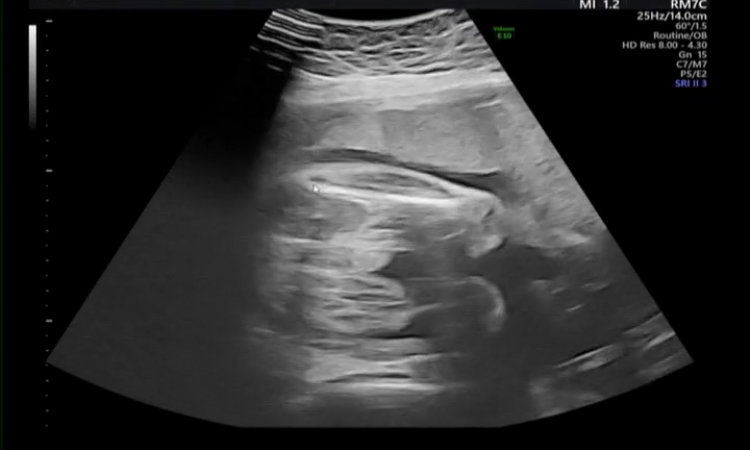

突然申し訳ないのですが、このエコーを見て、しっかり男の子の外性器はついているなと感じますでしょうか?。>_<。

性別は男の子と言われています。

実は先日、尿道下裂の可能性があるかも。と医師から言われました。

妊娠初期から見ていただいていた産院から、今は里帰り先の産院での検診になっているのですが、 元々見ていただいていた産院ではずっと男の子だね。と言われていました。エコーの写真も何枚かあります。

今、妊娠35週になるのですが、この時期に尿道下裂の指摘をされることはあるのでしょうか?😢